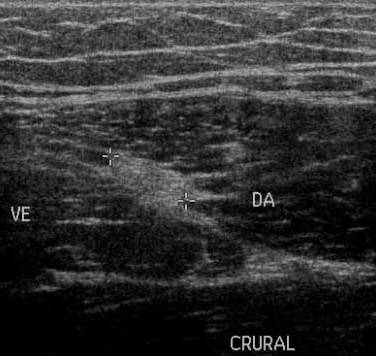

Stadiul IV Rodineau – ruptura la jonctiune mio tendinoasa

Echivalentul stadiului IV al lui Rodineau se caracterizeaza prin existenta unei rupturi sau unei dezinsertii musculo-aponevrotice complete cu,cel mai frecvent fascicol muscular retractat flotant intr-o cavitate hematica

Exista in aceste echivalente ale stadiului IV un caz particular, reprezentat de o ruptura osteotendinoasa (traumatismul spinei iliace antero-inferioare in leziunile dreptului femural la fotbalisti de exemplu